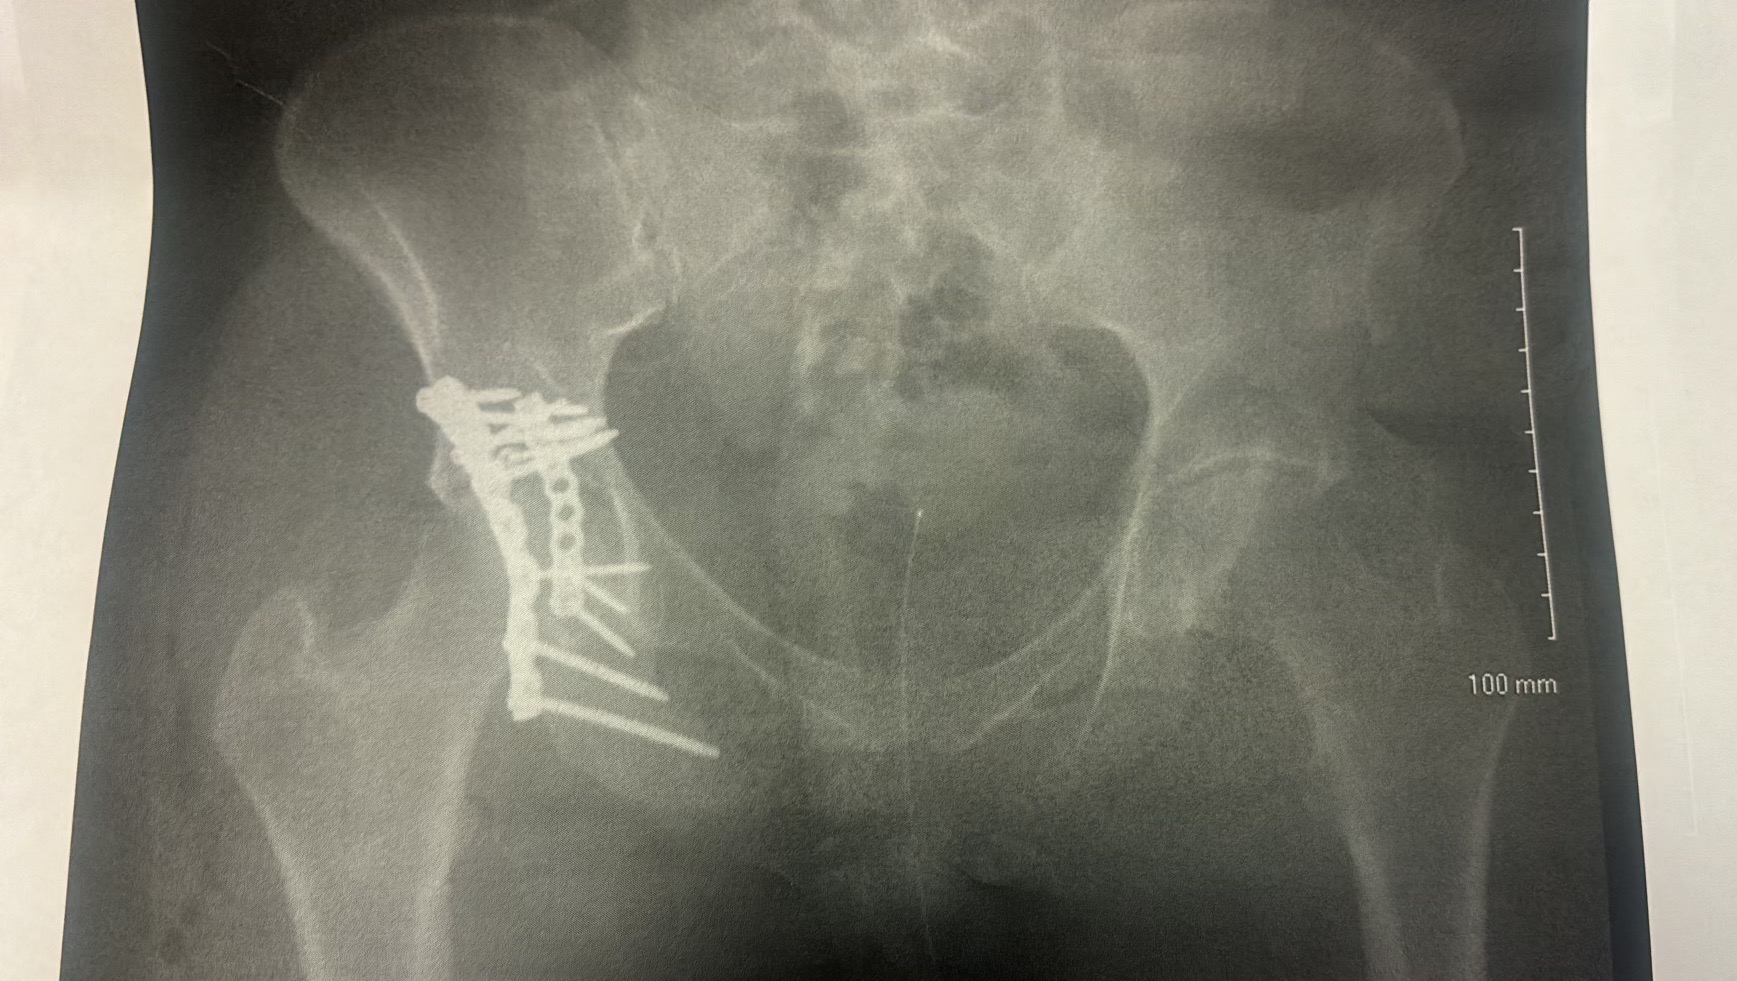

The accident caused a severe pelvic fracture, and she had to undergo a major surgery in which doctors stabilized her pelvis with 12 metal bolts and 2 metal plates. The procedure also required around 50 stitches.

El accidente le causó una fractura severa en la pelvis, por lo que tuvo que someterse a una cirugía mayor en la que los médicos estabilizaron su pelvis con 12 tornillos de metal y 2 placas metálicas. La operación también requirió alrededor de 50 puntos de sutura.